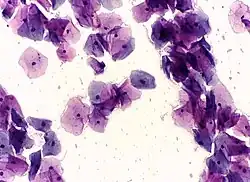

![]() High-grade squamous intraepithelial lesion | |

- High-grade squamous intraepithelial lesion (HGSIL or HSIL)